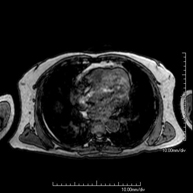

- Tòrax

- RM del Mediastí

Prova diagnòstica no invasiva que consisteix en l'obtenció d'imatges d'alta definició anatòmica del mediastí mitjançant l'ús d'un camp electromagnètic i ones de ràdio (amb un emissor i un receptor). No utilitza radiació ionitzant. El mediastí és la part central de la caixa toràcica que inclou el tim, els grans vasos (aorta toràcica, vena cava inferior i superior, etc.), el cor, la tràquea i els bronquis principals, els ganglis limfàtics mediastínics i hilars, l'esòfag, etc. Està especialment indicada en lesions mediastíniques per diferenciar si són quístiques o sòlides, en el diagnòstic diferencial de les lesions del mediastí anterior, etc. De vegades s'ha d'emprar contrast paramagnètic (Gadolini) per completar l'estudi. - RM Tòrax

Prova diagnòstica no invasiva que consisteix en l'obtenció d'imatges d'alta definició anatòmica del tòrax mitjançant l'ús d'un camp electromagnètic i ones de ràdio (amb un emissor i un receptor). No utilitza radiació ionitzant. Està indicada en aquelles lesions pulmonars en les quals s'ha de descartar si hi ha infiltració del mediastí o de la paret toràcica, per diferenciar si una lesió toràcica és sòlida o quística, etc. En alguns casos caldrà emprar contrast paramagnètic (Gadolini) per completar l'estudi. - RM de Paret Toràcica